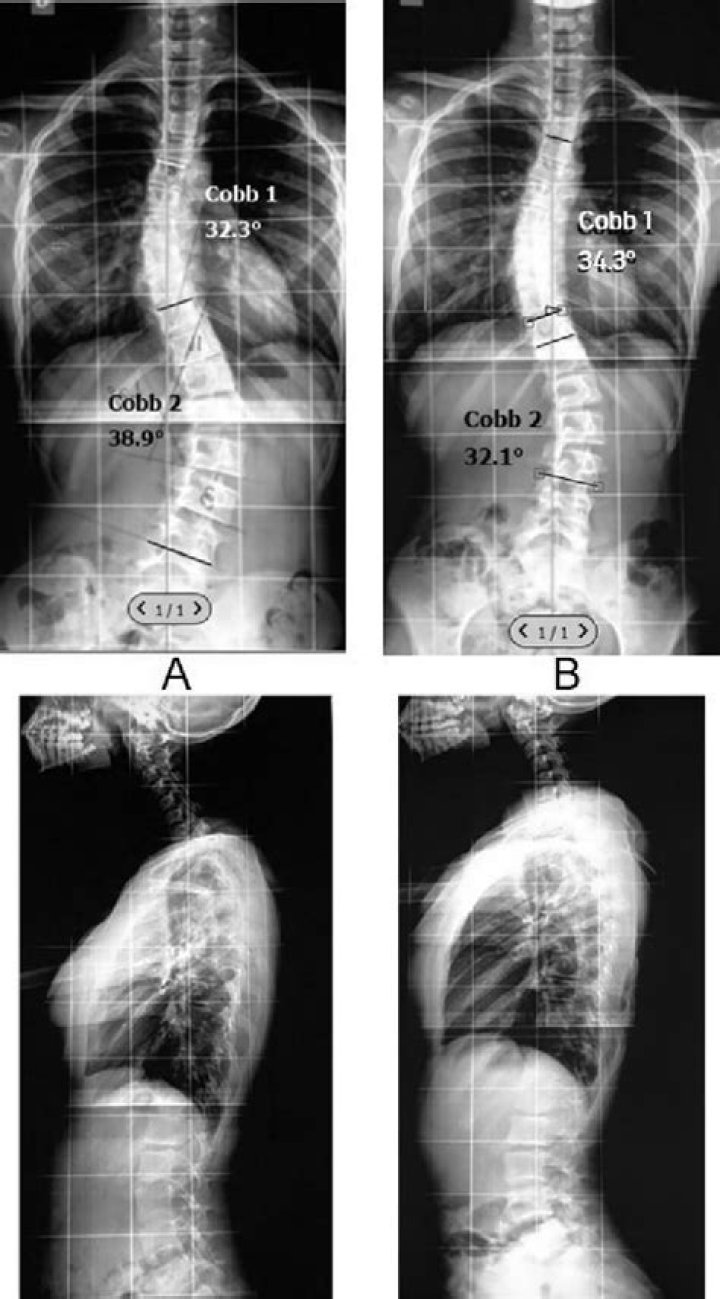

The Cobb angle is the most accepted method for measuring a scoliosis curvature. It's taken during a scoliosis X-ray and expresses the degree to which the spine bends, curves, and rotates away from a straight alignment. It's measured by finding the vertebrae (spinal bones) with the most tilt in each curve.

Health care providers measure scoliosis curves in degrees: A mild curve is less than 20 degrees. A moderate curve is between 25 degrees and 40 degrees. A severe curve is more than 50 degrees.

In general, a curve is considered significant if it is greater than 25 to 30 degrees. Curves exceeding 45 to 50 degrees are considered severe and often require more aggressive treatment.